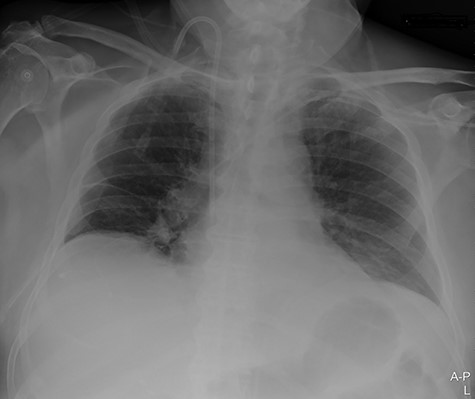

Our surgical team was contacted after 4 h, as the pleural fluid had become grossly haemorrhagic. A CXR showed haemothorax (Fig. 2). Upon clinical deterioration, the patient was intubated, and a 24Ch chest tube was introduced. Approximately, 500 ml of blood was immediately drained, followed by 300 ml during the first 30 min. ICA laceration was suspected. Despite transfusion of red blood cells and plasma and infusion of noradrenaline, the patient remained circulatory unstable. A new CXR showed massive haemothorax despite drainage (Fig. 3). The patient was now utterly haemodynamically unstable and not suited for transportation. As there are no thoracic surgeons or interventional radiologists in our hospital, the general surgeons decided to take him to the operating theatre. A wide anterolateral right thoracotomy was performed with patient lying in left lateral decubitus position. The right pleural cavity was full of fresh and coagulated blood. The pulsating bleeding was seen coming from the posterolateral, caudal chest wall, but the exact site deep down in the sharp costophrenic angle could not be localized and was inaccessible for any surgical haemostatic manoeuvre.

Portable chest X-ray in half-upright position showing haemothorax 4 h after placement of pigtail pleural drain.